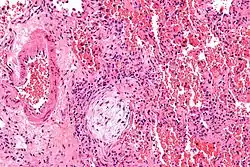

![]() | |

| Micrograph showing a Masson body (off center left/bottom of the image – pale circular and paucicellular), as may be seen in cryptogenic organizing pneumonia. The Masson body plugs the airway. The artery associated with the obliterated airway is also seen (far left of the image). H&E stain. | |

Organizing pneumonia is usually preceded by some type of lung injury that causes a localized denudation or disruption in continuity of the epithelial basal laminae of the type 1 alveolar pneumocytes that line the alveoli.[9] This injury to the epithelial basal lamina results in inflammatory cells and plasma proteins leaking into the alveolar space and forming fibrin, resulting in an initial fibroblast driven intra-alveolar fibroproliferation.[9] The fibroblasts differentiate into myofibroblasts and continue to form fibrosis resulting in intra-alveolar fibroinflammatory buds (Masson's Bodies) that are characteristic of organizing pneumonia.[9] These Masson's bodies consist of inflammatory cells contained in an extracellular matrix consisting of type I collagen, fibronectin, procollagen type III, tenascin C and proteoglycans.[9] Angiogenesis , or the formation of blood vessels, occurs in the Masson's bodies and this is driven by vascular endothelial growth factor.[9] Remodeling occurs, resulting in the intra-alveolar fibroinflammatory buds (Masson's Bodies) moving into the interstitial space and forming collagen globules that are then covered by type 1 alveolar epithelial cells with well developed basement membranes. These type 1 alveolar epithelial cells (pneumocytes) then proliferate, restoring the continuity and function of the alveolar unit.[9] This process is in contrast to the histopathologic changes seen in usual interstitial pneumonia where extensive fibrosis and inflammation occur leading to fibroblastic foci to form in the alveolar spaces resulting in obliteration of the alveolar space, scarring and significant damage to lung architecture (the alveoli).[9]

Biopsy findings in patients with organizing pneumonia consist of loose connective tissue plugs involving the alveoli, alveolar ducts and bronchioles. The loose connective tissue plugs occupying the alveolar spaces often connect to other connective tissue plugs in nearby alveoli via the pores of Kohn creating a characteristic butterfly pattern on histology.[9] There is usually minimal to no interstitial inflammatory changes in biopsies of organizing pneumonia.[9]

Histologically, cryptogenic organizing pneumonia is characterized by the presence of polypoid plugs of loose organizing connective tissue (Masson bodies) within alveolar ducts, alveoli, and bronchioles.